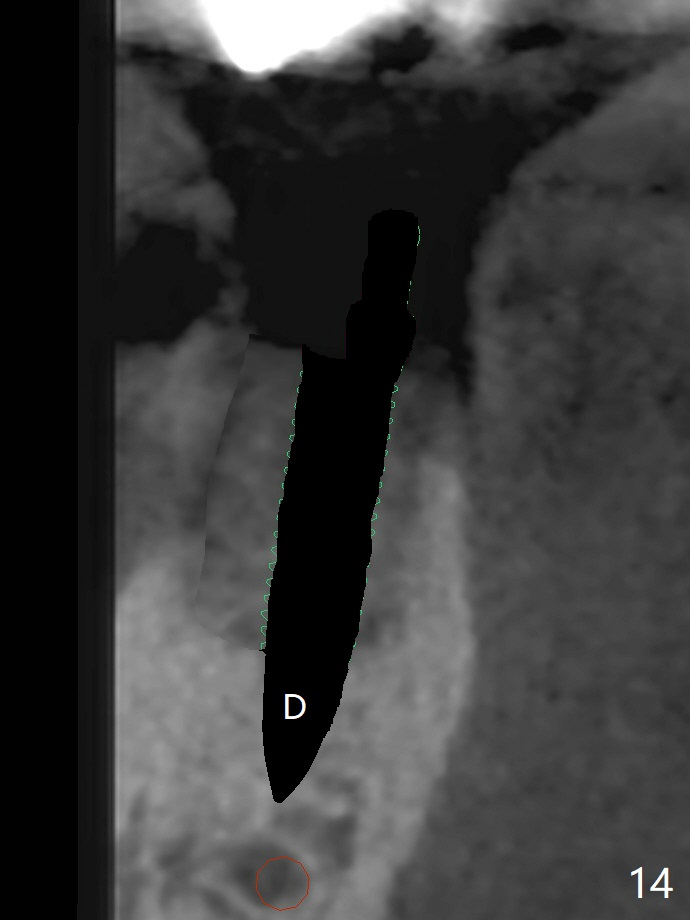

A 88-year-old man returns with pain and swelling (Fig.1), one year after diagnosis of #31 mesial root fracture. After discussion, the tooth is extracted with socket preservation (Vanilla graft mixed with Osteogen, covered with Osteogen plug and Collagen plug, Fig.2,3). The buccal crest is much lower than the lingual one. The socket opening reduces with resolution of 4-0 Chromic gut suture 1 week postop (Fig.4). The wound is wider with foul odor 2 weeks postop (data not shown). The socket and ridge shrink with loss of the bone graft 3 weeks postop (Fig.5). The bone volume reduces with buccal plate collapse 3 months postop (Fig.6,7). Immediate implant and provisional should be able to help restore the lost buccal plate. The buccal plate remains concave 5 months postop (Fig.8,9). The coronal section shows that there is space (Fig.10 *) buccal to the graft (G). A 2.0 mm pilot drill is used to create an initial osteotomy through the graft zone and in the beginning of the native bone (Fig.11,12). Use bone expanders (Fig.13 E) to push (arrowheads) and condense the graft bone and close the buccal gap. The apical portion of the osteotomy requires regular drills (Fig.14 D).